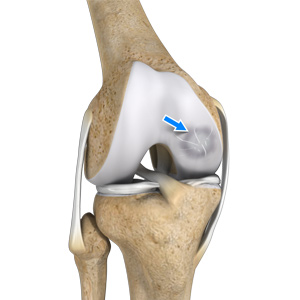

Osteochondral Defect of the Knee

An osteochondral defect, also commonly known as osteochondritis dissecans, of the knee refers to a damage or injury to the smooth articular cartilage surrounding the knee joint and the bone underneath the cartilage. The degree of damage may range from a rupture of the cartilage to a slight crack of the bone to a piece of the bone breaking off within the joint.